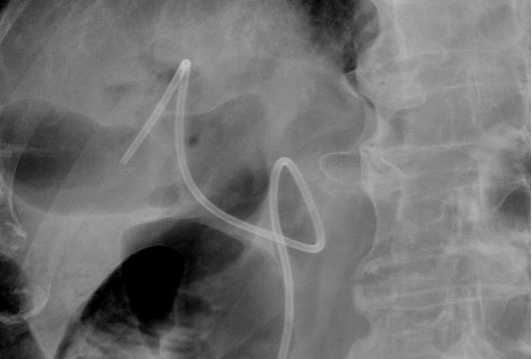

EUS-GE 对医生的操作精准度、临床经验和应急处理能力要求极高。目前国内EUS-GE 临床应用尚未普及,仅部分发达地区大型医院具备开展该技术的条件。该手术操作过程中需实时通过超声定位,避开血管、肝脏等重要脏器,同时确保吻合口牢固、通畅,避免出血、穿孔等并发症的发生。为此,消化内科内镜医生、麻醉医生及护理团队提前制定了详细的手术预案,11日下午为张大爷施行了手术。术中医护团队密切配合、精准操作,应用胃镜将超滑导丝送入狭窄远端肠管,在X线定位下送入球囊封堵远端空肠,注入造影剂使空肠近端显影,使用超声内镜在胃腔内定位,将双蘑菇头支架精准置入空肠与胃之间,仅用 40 分钟就顺利完成通道建立,全程无出血、无并发症发生。

X线下见支架在位